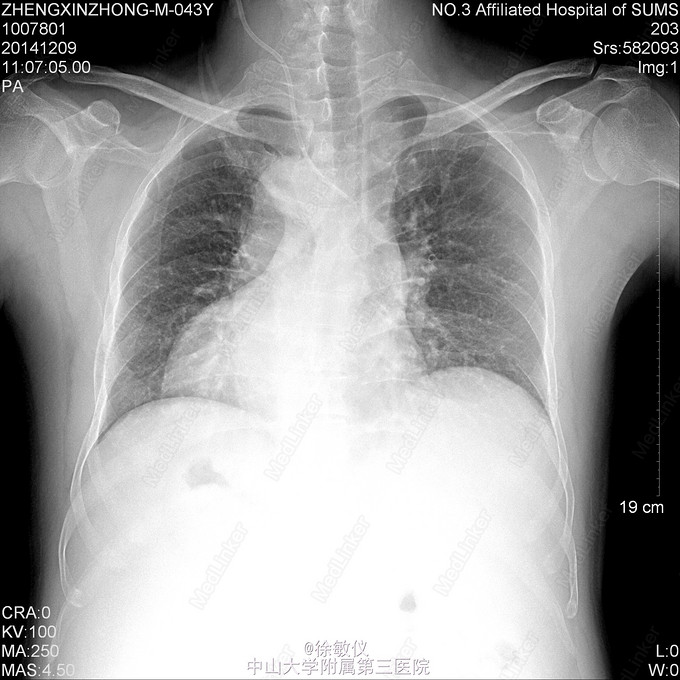

发现一个有意思的胸片。。。

这是先天性脏器反位,罕见的解剖结构异常。